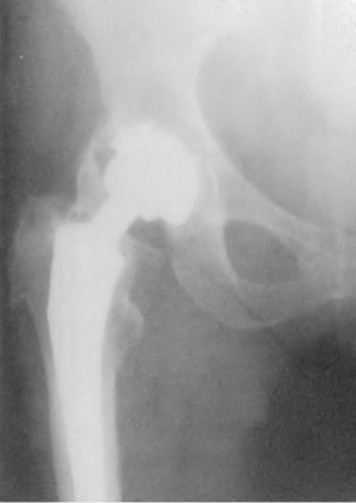

A 67 year-old woman sustained an ACL tear while playing basketball when she was 35 years-old. She has noted progressive leg deformity and episodes of giving way, and now has pain preventing activity. Non-operative management has failed to provide relief. Treatment should consist of?

The radiograph seen in Figure A reveals varus alignment of the knee, with medial tibial deficiency; from this X-ray the patient appears to have unicompartmental arthritis. Treatment options for unicompartmental arthritis include high tibial osteotomy, interpositional arthroplasty, unicondylar knee replacement and total knee replacement. Interpositional arthroplasty became popular in the 1950’s when early outcomes analysis seemed to indicate good results; long term follow up in one study found 0/12 excellent results, with all patients requiring conversion to TKA. This procedure is no longer recommended due to the poor long term outcomes.

While an osteotomy is still used for young and active patients, unicompartmental or total knee arthroplasty have largely replaced this treatment in older patients. Advantages of UKA and TKA include more predictable relief of pain, quicker recovery, and better long-term results. Criteria for UKA include limited unicompartmental disease, no more than a fixed 10 degrees of varus or 5 degrees of valgus deformity from neutral and an intact anterior cruciate ligament with no signs of medial lateral subluxation of the femur on the tibia; this patient is therefore not a good candidate for this procedure.

Total knee arthroplasty can be used to provide predictable pain relief in a patient with unicompartmental and tricompartmental degenerative disease and varus malformation of the knee and for this patient is the best option.